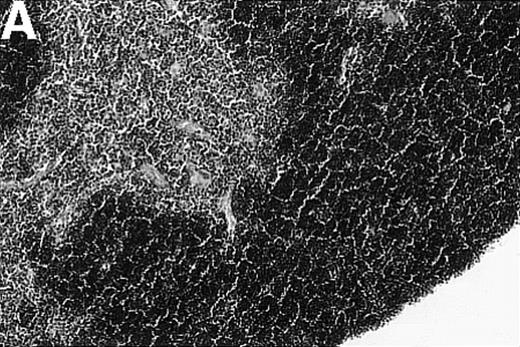

To investigate whether acute or chronic GVHD affects the thymic architecture, an unirradiated P→F1 hybrid model was chosen. After B6→B6D2F1 transplantation, acute GVHD developed, and the thymuses of recipient mice displayed severe morphologic changes (Figure 1). Two weeks after transplantation, the size of the thymus was decreased, and the loss of a regular thymic architecture was apparent with a clear lack of a demarcation between cortex and medulla. In the course of the disease, thymic cellularity progressively decreased and did not recover until the animal's death approximately 4 weeks after transplantation (Figure1D). In contrast, the thymic architecture was not overtly altered during chronic GVHD (DBA/2→B6D2F1). Correspondingly, thymic cellularity was not diminished from this disease when it was analyzed between 1 and 4 weeks after transplantation.

Thymic disease is a consequence of acute but not chronic GVHD.

Acute GVHD was induced by the transfer of 50 × 106parental B6 splenocytes to unirradiated B6D2F1 mice (B), whereas chronic GVHD was induced by the transfer of 80 × 106 parental DBA/2 splenocytes to unirradiated B6D2F1 mice (C). Syngeneically transplanted B6D2F1 mice served as controls (A). Frozen thymic sections (5 μm) were analyzed for histopathology at 2 weeks after transplantation. Magnification ×200. (D) Thymic cellularity as a function of time (total cells per thymus × 10−6) in syngeneically transplanted mice (▵) and in mice with acute (•) and chronic (□) GVHD, respectively. The figure represents combined data (mean ± SEM) of individual mice from at least 8 separate experiments; 20 to 42 mice were analyzed for each group.